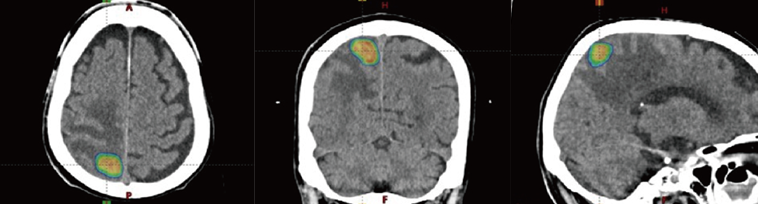

主に脳や肺・肝臓の「小さい病変」を対象に、いろんな方向から非常に高い線量をピンポイントで患部に当てる方法。1~数回の照射で高い効果を出すことができ、患部を「焼き切る」イメージで外科手術の代わりに使われることの多い手法です。肺がん患者さんの場合、手術より高いQOL(生活の質)を維持できるというアンケート結果も。

1回当たりの線量が多いため、照射中にじっとしていなくてはいけない時間が長く、患者さんの体形などに合わせたオーダーメイドの固定具でサポートします。保険上の制約はありますが、転移があっても照射でき、近年少しずつ適用範囲が広くなってきています。